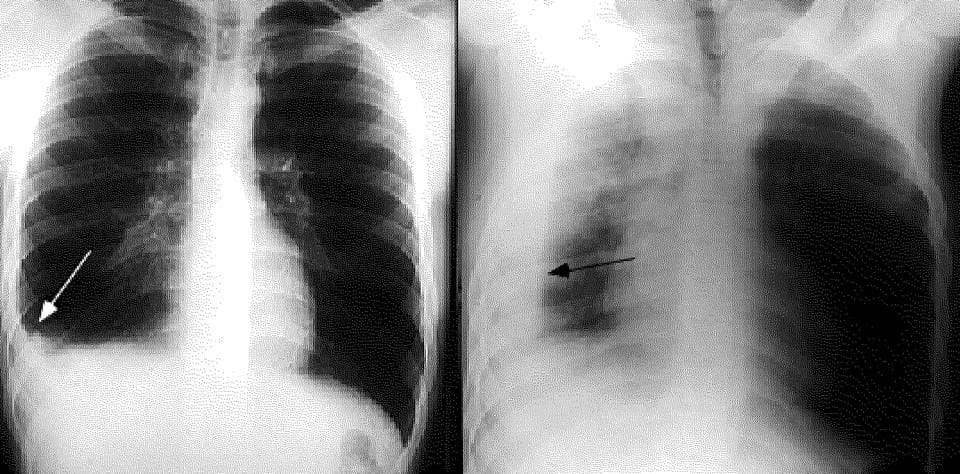

Tràn dịch màng phổi là gì? Bệnh này có nguy hiểm không?

Tràn dịch màng phổi là bệnh lý nguy hiểm có thể gặp ở mọi lứa tuổi, ngay cả trẻ em, tuy nhiên bệnh tỏ ra nguy hiểm hơn ở người cao tuổi. Vì vậy cần phát hiện sớm và điều trị kịp thời. vậy tràn dịch màng phổi là gì? Tràn dịch màng phổi là […]

Tràn dịch màng phổi có thể là di chứng của nhiều bệnh lý nguy hiểm khác nhau, việc điều trị tràn dịch màng phổi phụ thuộc vào từng nguyên gây bệnh. Bài viết dưới đây sẽ cung cấp thông tin cụ thể những nguyên nhân gây tràn dịch màng phổi. Màng phổi gồm hai lá […]